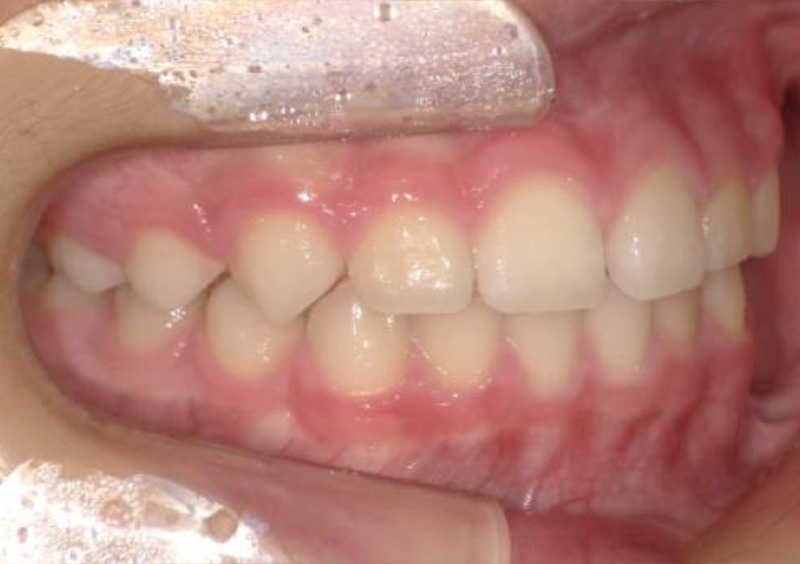

子供の矯正治療 大人の歯が生えてくるスペースがない 2026.03.19 【プレオルソ】大人の歯が生えてくるスペースがない 治療前 治療後 担当医 一瀬 悠依華 先生 主訴 大人の歯が生えてくるスペースがない 期間 4年 費用 35万円(小児矯正) 治療内容 プレオルソ 治療に伴うリスク 歯根吸収、歯肉退縮 関連症例